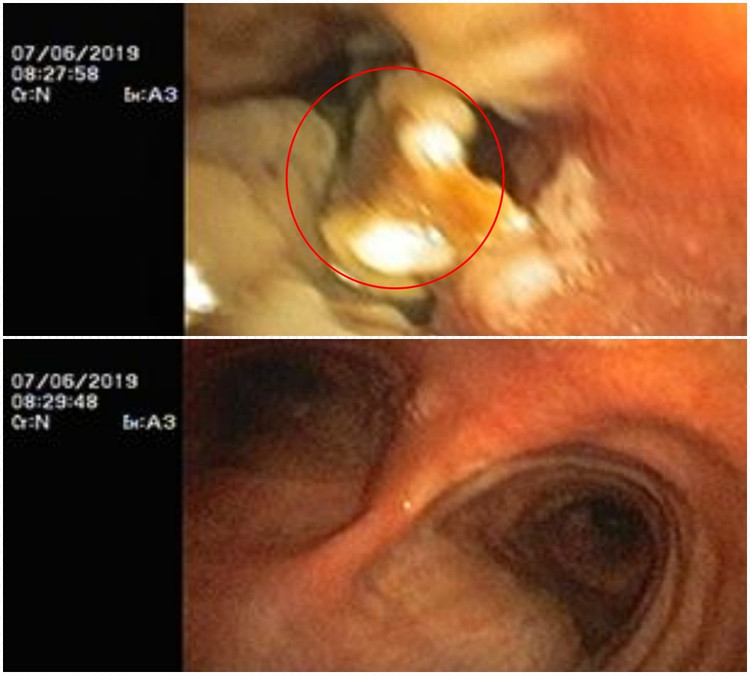

Kết quả chụp cắt lớp lồng ngực cho thấy hình ảnh dị vật sắc nhọn ở vị trí phế quản đáy trái. Bệnh nhân được chỉ định nội soi phế quản cấp cứu lấy dị vật.

Kíp bác sĩ khoa Hô hấp và Bệnh nghề nghiệp đã tiến hành nội soi phế quản dưới gây mê và gắp thành công dị vật là 1 chiếc đinh vít dài khoảng 1 cm có đầu sắc nhọn.

| Hình ảnh đinh vít trong phế quản bệnh nhân và được lấy ra - Ảnh BVCC |